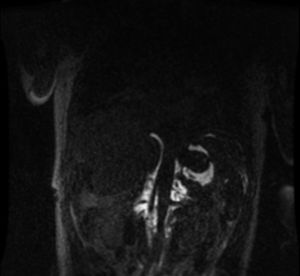

Once all the possible secondary medical etiologies potentially causing this condition had been ruled out, magnetic resonance lymphography was performed, which detected an abdominal mass with a craniocaudal diameter of 11 cm that had not been observed on the initial computed tomography scan. The lesion extended from the celiac vessels up to the renal hila surrounding the abdominal aorta in early phases (Fig. 1), with extravasation of the contrast agent into the abdominal cavity in late phases (Fig. 2).

The clinical-radiological diagnosis of bilateral chylothorax was established, in association with chylous ascites resulting from spontaneous rupture of a retroperitoneal lymphangioma.